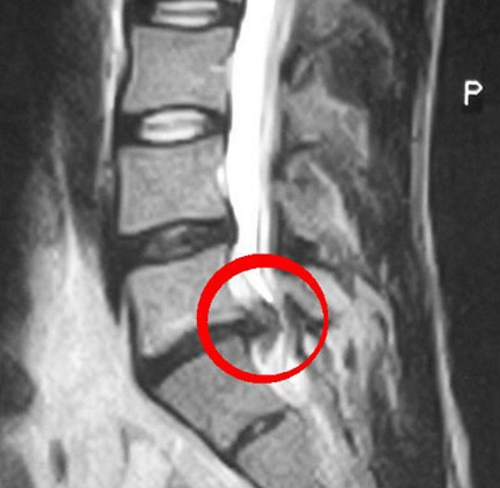

Ортопед проведет МРТ для получения точных данных о размере и расположении грыжи. При необходимости может быть предложено хирургическое вмешательство.

Диагностика у беременных имеет свои сложности, так как возможности обследования ограничены. Если грыжа проявилась в первом триместре, возможно проведение УЗИ и анализов крови. МРТ используется на более поздних сроках, только если грыжа угрожает здоровью ребенка.